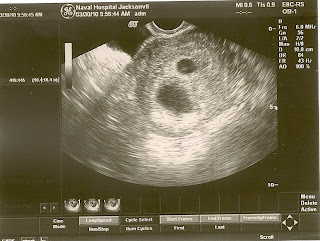

So, we had our first ultrasound today, and we are excited to announce that it's TWINS!!!

As the doctor was doing the ultrasound we right away saw two sacks of fluid, but it was hard to make out if anything was in the sacks. As the doctor moved the ultrasound around, the 1st heartbeat jumped out at us (confirming one). I was relieved to see that heartbeat, because up until then, I was starting to worry again that maybe I wasn't pregnant. I have just felt so normal so far, with only mild occasional nausea, "knock on wood"... :)

She moved the ultrasound to the second sack & was trying to visualized if anything was in there. Then, all of a sudden at the very bottom of the little sack of fluid, there was another tiny little speck with a heartbeat beating away! I couldn't believe it, and from my angle I couldn't really see the heartbeat at first, but Phil said he saw it right away, clear as day. Before seeing the heartbeat, I was thinking the 2nd bag of fluid was part of my swollen fallopian tubes, and I was waiting for the doctor to say, "no, that must be just part of the ......" But instead, she said, "yes, there is definitely a second heartbeat. " Phil and I looked at each other with a look of half excitement & half shock! We both said, just wait till we tell our parents!!

The doctor measured the babies, and one baby measured 6 weeks 3 days, and the other measured 6 weeks 4 days. According to my invetro cycle I should be 7 weeks 1 day, so we questioned how the days could be so far off. The doctor really didn't have an answer, but she wants to see me back in 2 weeks (14 April) for a confirmation of dates ultrasound. As of now, my due date is Halloween for twins or November 20th for one child. She also recommended that I schedule a planned c-section, because of my extensive surgical history and all my scar tissue. She is worried that if I attempt a vaginal delivery and end up needing an emergency c-section, that it will be harder to get to the babies quick enough, and could cause them/me more harm. If the c-section is planned, she will go through my old scar and have a general surgeon in the room to help out.